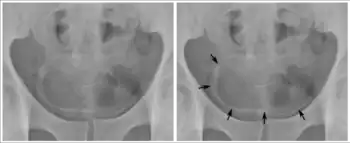

Os ovos podem ficar alojados no fígado,[25] levando a hipertensão portal, esplenomegalia, acúmulo de líquido no abdômen e risco de vida potencial dilatações ou áreas inchadas no esôfago ou trato gastrointestinal que podem rasgar e sangrar profusamente (varizes esofágicas). Esta condição pode ser dividida em duas fases distintas: esquistossomose hepática inflamatória (reação inflamatória precoce) e esquistossomose hepática crônica. As espécies mais comuns que causam esta condição são S. mansoni, S. japonicum, e S. mekongi.

- Esquistossomose hepática inflamatória

- Esta condição ocorre principalmente em crianças e adolescentes devido à reação imune precoce aos ovos presos nos espaços periportal e pré-sinusoidal do fígado, criando numerosos granulomas.[14] A função hepática não é afetada e a gravidade da doença o aumento do fígado e do baço está correlacionado com a intensidade da infecção.[14] Caracteriza-se por um lobo esquerdo do fígado aumentado com uma borda afiada e baço aumentado com nódulos.[28] O aumento do fígado e baço geralmente é leve, mas em casos graves, eles podem aumentar até o nível do umbigo e até mesmo na pelve.[14]

- Esquistossomose hepática crônica (fibrótica)

- Esta é uma doença hepática em estágio avançado que ocorre principalmente em adultos jovens e de meia-idade que foram infectados cronicamente por uma infecção grave e cuja regulação imunológica da fibrose não está funcionando adequadamente.[14] Afeta apenas uma pequena proporção de pessoas infectadas.[14] A função e a arquitetura do fígado não são afetadas, ao contrário da cirrose.[14] A patogênese dessa doença é causada pela deposição de colágeno e proteínas da matriz extracelular dentro do espaço periportal, o que leva à fibrose portal do fígado e tratos portais fibróticos aumentados (fibrose da haste do tubo de Symmer).[26] A fibrose periportal comprime fisicamente a veia porta levando a hipertensão portal (aumento da pressão venosa portal), aumento da pressão da veia esplênica e subsequente aumento do baço.[14] A hipertensão portal também pode aumentar a pressão nas anastomoses portossistêmicas (conexões de vasos entre a circulação portal e a circulação sistêmica) levando a varizes esofágicas e caput medusae. , ou cérebro.[14] A co-infecção com hepatite é comum em regiões endêmicas de esquistossomose com hepatite B ou hepatite C, e a co-infecção com hepatite C está associada a deterioração hepática mais rápida e pior prognóstico .[26] Esquistossomose hepática fibrótica causada por S. mansoni geralmente se desenvolve em cerca de 5 a 15 anos, enquanto pode levar menos tempo para S. japonicum.[14]

A ultrassonografia em mãos experientes pode fazer o diagnóstico, sendo patognomônico a fibrose e espessamento periportal, hipertrofia do lobo hepático esquerdo e aumento do calibre da mesentérica superior.[33]